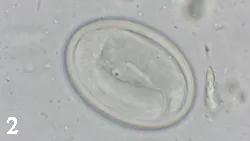

A magnified view of a roundworm egg, displaying its oval shape and distinct outer shell structure, observed under a microscope. The egg is surrounded by a clear background with some debris, indicating a laboratory setting for parasitological examination.

Centrifugation fecal flotation using Sheather’s sugar solution (specific gravity, 1.27), which is now commercially available, can recover more eggs with a mean specific gravity above <sup1.2,sup> such as Taenia (Figure 1) and Physaloptera species (Figure 2), than standard salt solutions (eg, zinc sulfate and sodium nitrate; specific gravity, 1.18–1.2). Sodium nitrate solutions can be made with higher specific gravity, but slides must be examined quickly before solution crystallizes.